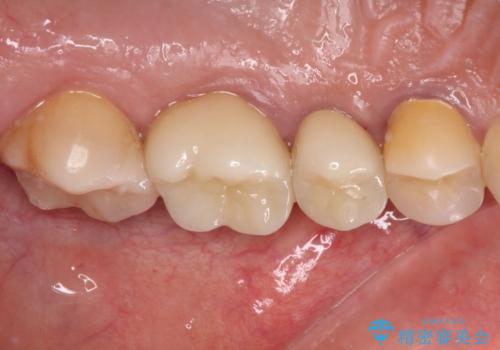

億劫に感じて治療を先延ばししていたそうですが、始めてみるとスムーズに治療が終わり、早く始めておけば良かったと仰っていました。

他にも加療の必要な歯があるので、定期健診を行いながら再開していく予定です。